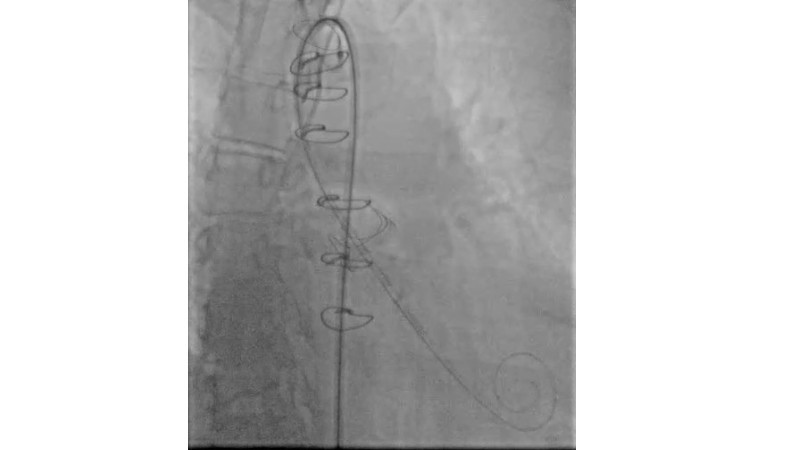

This session explores the evolving landscape of transcatheter aortic valve implantation (TAVI) with a focus on supra-annular valve technology. It covers techniques for achieving commissural alignment, considerations for small aortic annuli, and advantages in treating bicuspid aortic valve disease, supported by clinical data and illustrative cases.

- To learn how to perform TAVI resulting in commissural alignment and easier coronary access